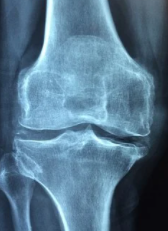

중년의 나이쯤 되면 뼈 건강과 골다공증 걱정을 하지 않을 수 없는데요. 뼈 건강에 좋은 하늘 마의 효능과 먹는 법을 통해서 약해져 가는 뼈 건강을 튼튼하게 지켜내는 것은 어떨까요.

몸의 허약함을 느끼거나 골다공증 및 뼈 건강으로 생활에 불편함이 있으신 분들은 하늘 마를 접해보시는 것이 많은 도움이 될 거라 생각합니다. 아래 소개하는 하늘 마 효능과 먹는 법에 대해 천천히 읽어보시는 것을 추천드립니다.

하늘 마는 동의보감에서 그 효능을 얘기할 정도로 예부터 뼈 건강에 효능이 있는 것으로 알려져 있습니다. 동의보감 속 하늘 마에 대한 이야기를 간단히 하면 "몸이 허약하고 과로한 것을 보강해 근육과 뼈를 강하게 만들어준다"라고 소개하고 있습니다. 몸에 좋은 약재료의 경우 대부분이 이 동의보감에서 이미 거론이 되는 경우가 많습니다.

하늘 마는 일반 마와 달리 칼슘 성분이 3배나 더 많이 함유되어 있다고 합니다. 때문에 뼈와 골다공증에 좋다고 하는 것인데요.

하늘 마는 몸속 혈류량을 증가시켜주고 근육에 산소와 영양분을 공급해주기 때문에 뼈 건강에 좋다고 하는데요. 원기 보충과 신장을 튼튼하게 하여 체내 산화질소의 생성을 촉진시켜 주는 역할을 한다고 합니다. 이 뿐만 아니라 열매 마의 효능은 10여 가지가 넘을 정도로 다양한데요.